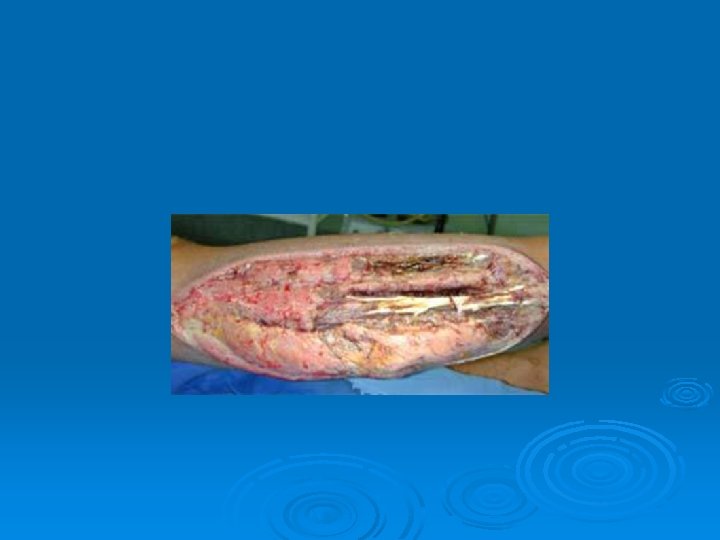

Compartment Syndrome Ø MX: l Ø S/S: l Ø Deep aching pain, tightness, and swelling. Pain with stretching. TX: l l Ø Increased pressure within one of four compartments of lower leg causes compression of the structures in the leg. Acute~ immediate surgery Chronic~ activity modification & ice and some times surgery Prevention: l Stretching (Hard to prevent)